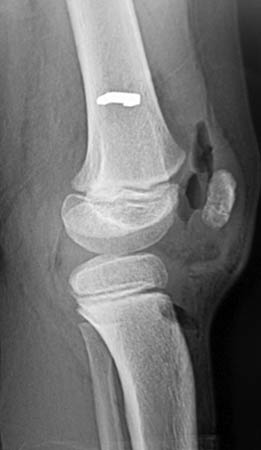

Los estudios por imágenes en casos de dolor en la cadera deben comenzar por las RX simples, pelvis frente, caderas panorámica frente, tomadas según el método de Siebenrock et al.13 (15° de rotación interna con la distancia entre la sínfisis pubiana y el coxis de 32mm en los hombres y 47mm en las mujeres), perfil quirúrgico bilateral y perfil de Louestein y el perfil de Lequesne (falso perfil) permite evaluar cobertura anterior en posición fisiológica. La correcta interpretación de estas imágenes y su correlación con el cuadro clínico, nos van a sugerir la necesidad de otros estudios que nos permitan aclarar el diagnóstico: la tomografía computada con reconstrucción tridimensional (TAC 3D), la RMN sin contraste. En la actualidad solicitamos siempre RX de pelvis frente, caderas panorámica, perfil quirúrgico, perfil de Dunn, (caderas en 90° de flexión y 20° de abducción), TAC 3D y en casos seleccionados la RMN con contraste (Figs. 4, 5, 6, 7a y 7b).14, 15, 16

Figura 4: RX Frente.

Figura 7b: Rx de un paciente de 48 años con cartílago aparentemente sano y calcificación del labrun.